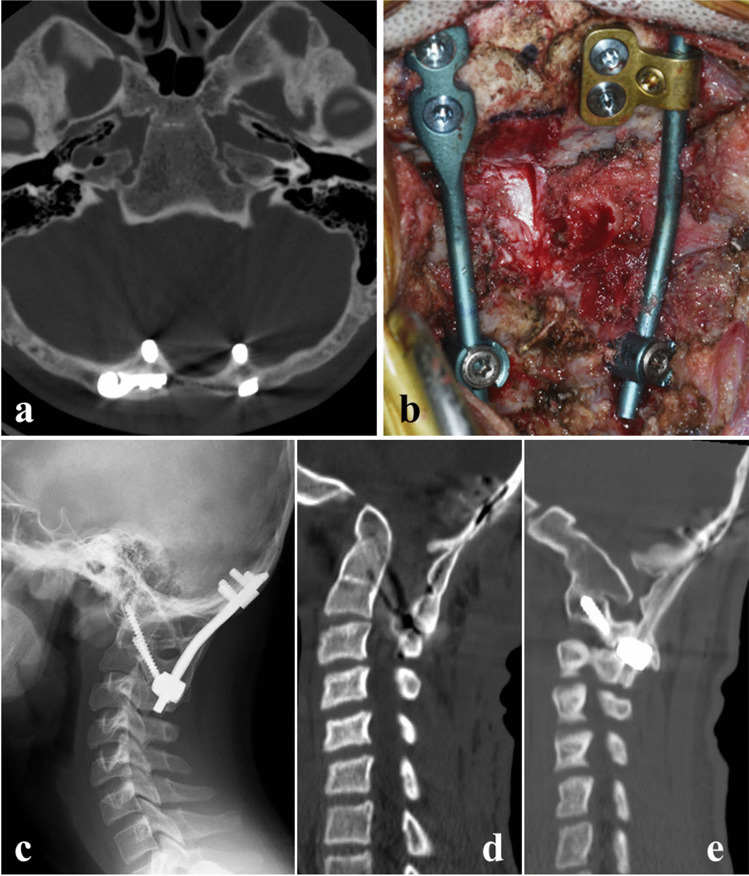

The neurological impairment was partially attributed to upper cervical instability associated with os odontoideum because of partial neurological symptom improvement by the halo vest immobilization. Hence, we performed in situ O-C2 fusion using an iliac autograft and decompression of the foramen magnum and posterior arch of C1, in lieu of reducing the congenital atlanto-occipital dislocation. Due to a bifurcated internal occipital crest with a thinned central portion of the occipital bone, we bilaterally placed the occipital plates separately (Fig. 3a, b). The neurological impairment improved immediately after surgery, and the patient showed no myelopathy 2 years after surgery. Radiography and computed tomography demonstrated solid O-C2 segment fusion, including fusion of the os odontoideum to the base of the axis (Fig. 3c–e).

Fig. 3.

Surgery for upper cervical myelopathy caused by a congenital atlanto-axial dislocation complicated by os odontoidum. a Postoperative axial computed tomography demonstrating occipital screws placed bilaterally into the bifurcated internal occipital crests. b Intraoperative photograph showing decompression of the foramen magnum and posterior arch of C1 with occipital plates separately placed bilaterally. c Lateral radiograph of the cervical spine 2 years after surgery. d, e Sagittal reconstruction computed tomography 2 years after surgery showing solid fusion of the O-C2 segment. Note that the os odontoideum is fused to the base of the axis